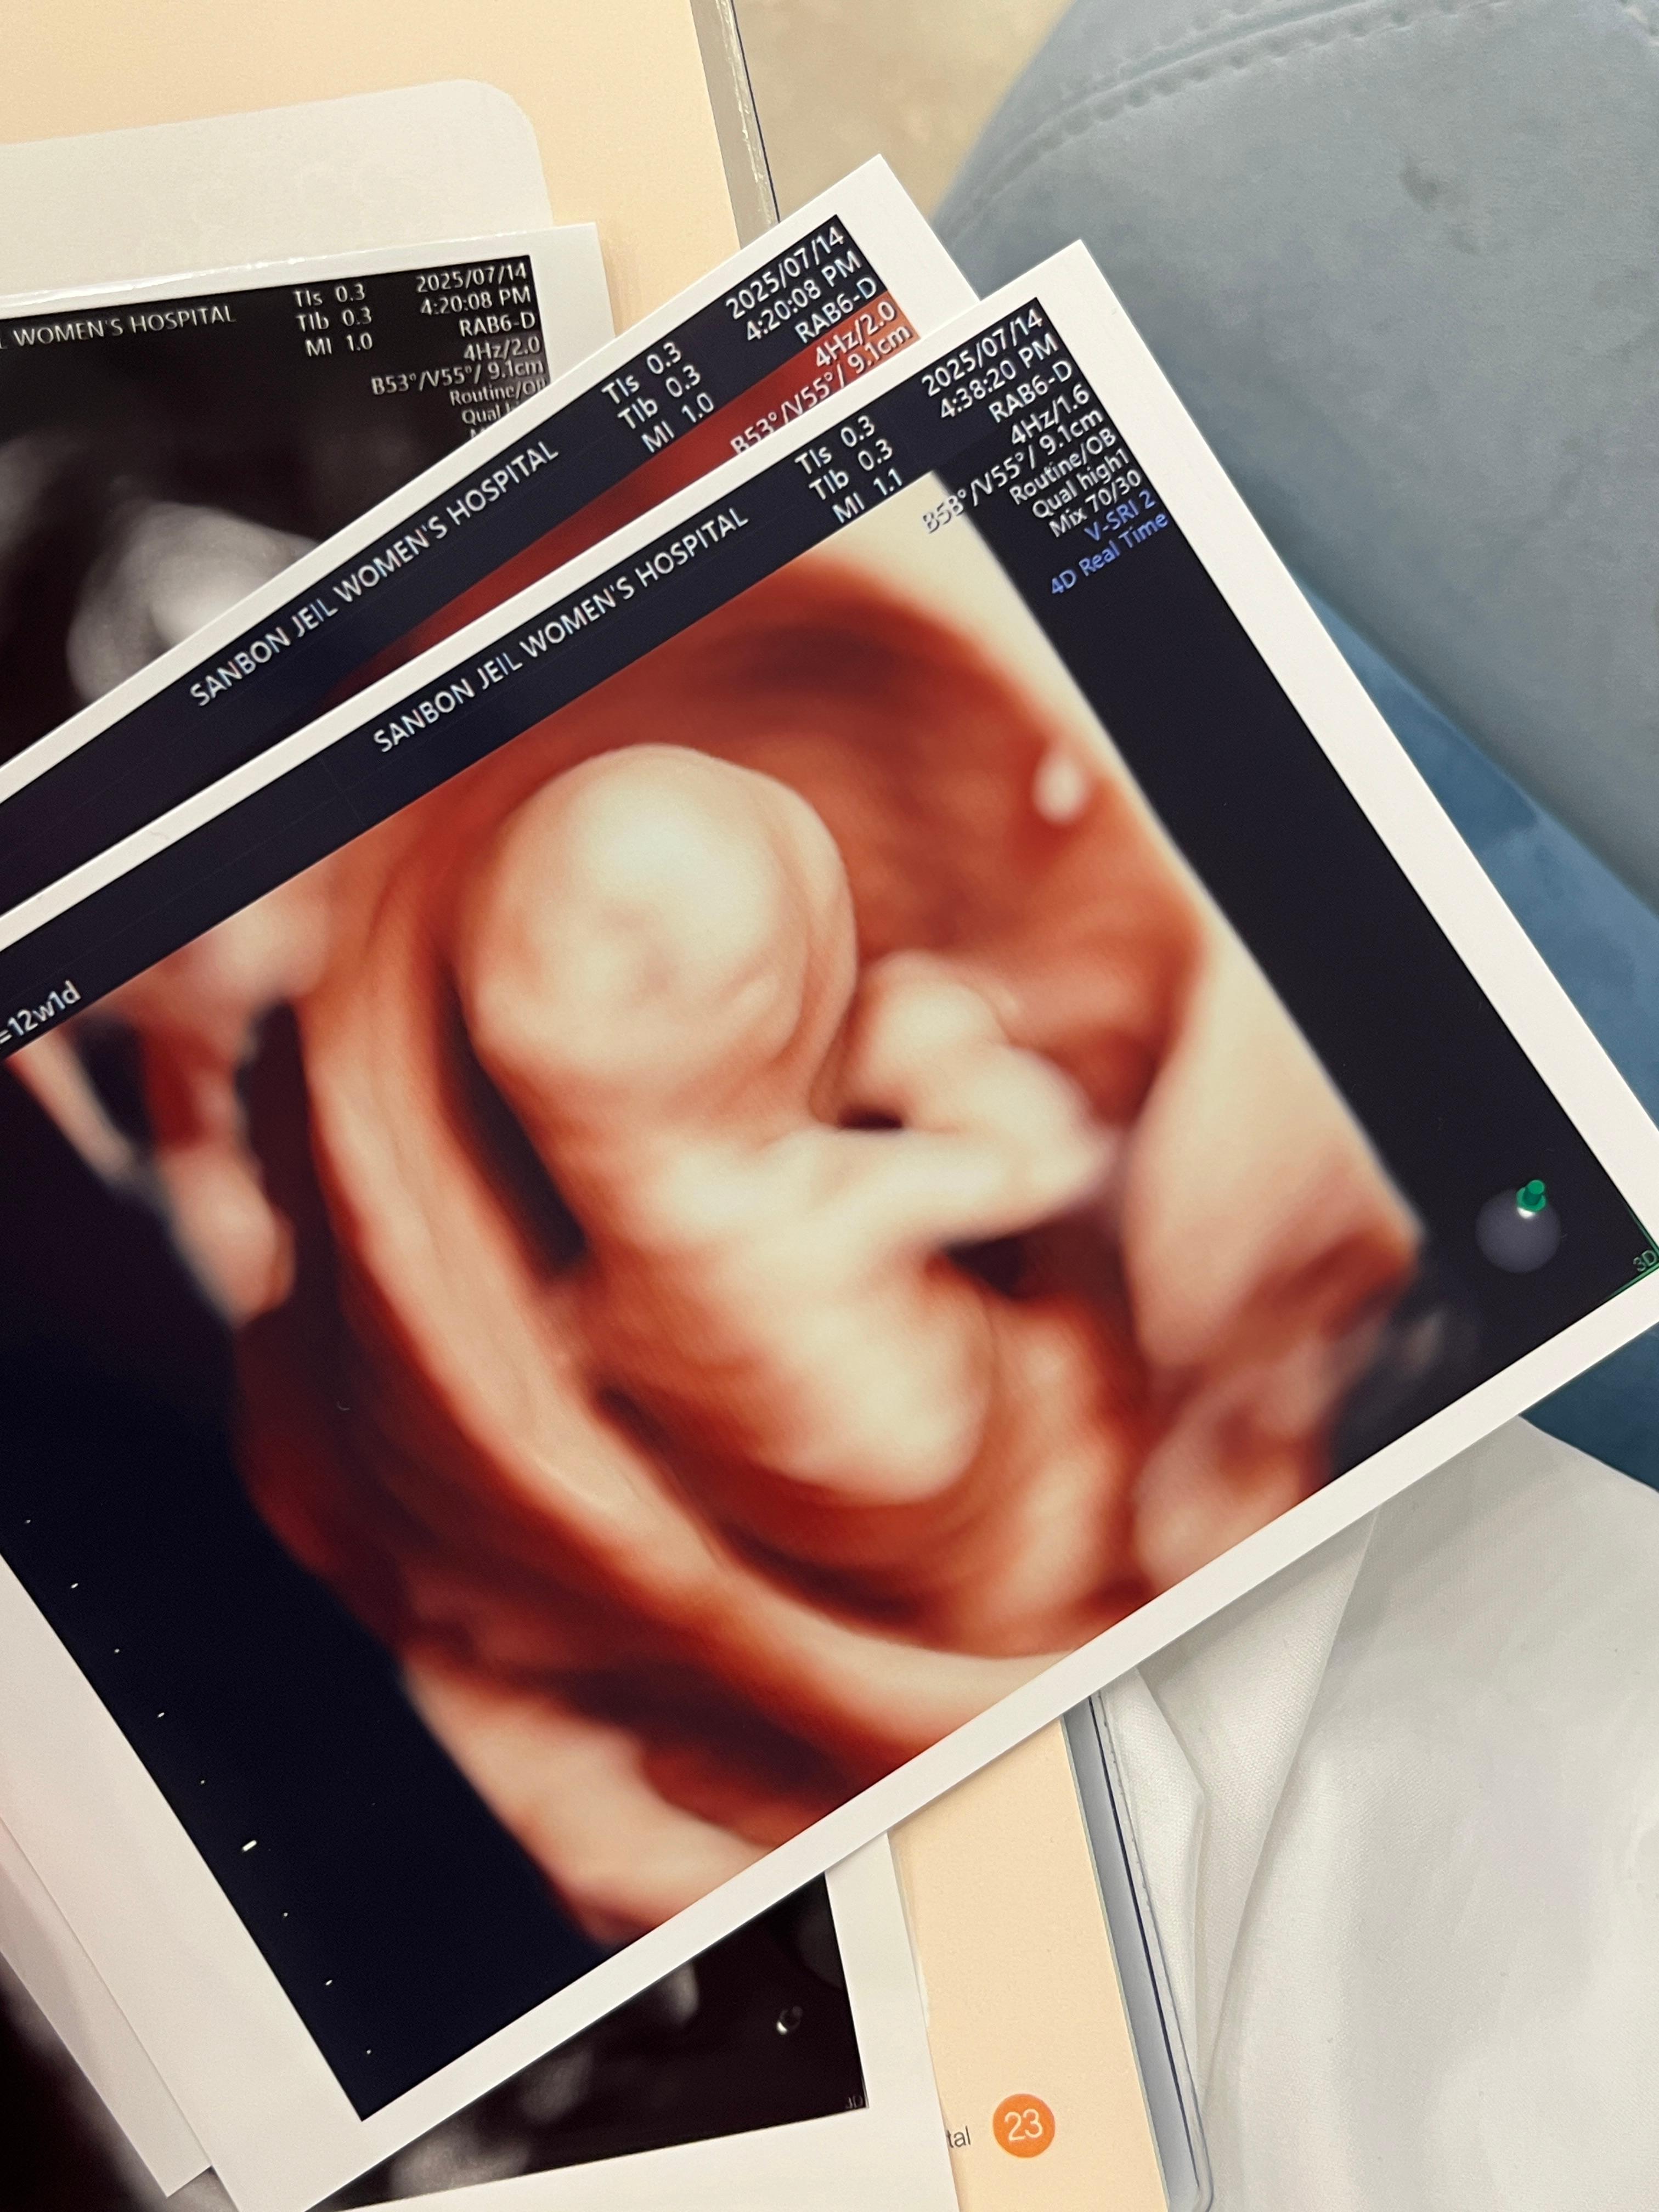

임신초기 12~13주에 시행하는 초음파는 태아 목덜미 검사로 염색체 이상에 대한 선별 검사에요!

요즘에는 의료기술이 발달해서 목덜미 투명대 검사만으로도 태아가 기형아인지 문제가 있는지를 알 수 있다고 하더라고요

이렇게 사진도 주시는데 제 아기는 뒤로 돌아있어서 등만 보고 왔네요

기형아검사 1차 정밀초음파는 정말 금방봐요 아기가 작기때문에 크게 볼 것도 없고..